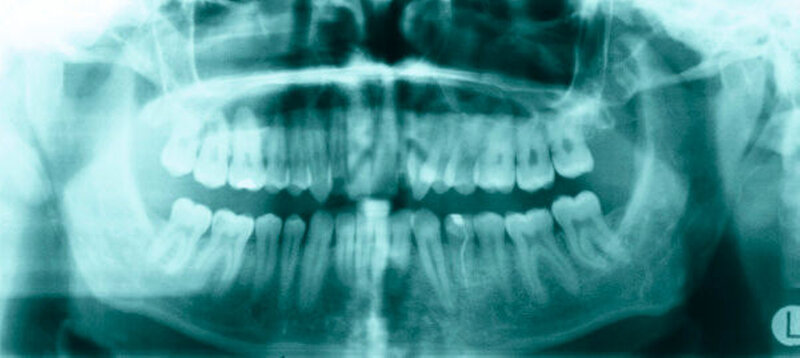

Bei der Befundung des Orthopantomogramms fielen hyperplastische, weit nach cranial extendierende Processus (Proc.) coronoidei beidseits auf (Abbildung 2).